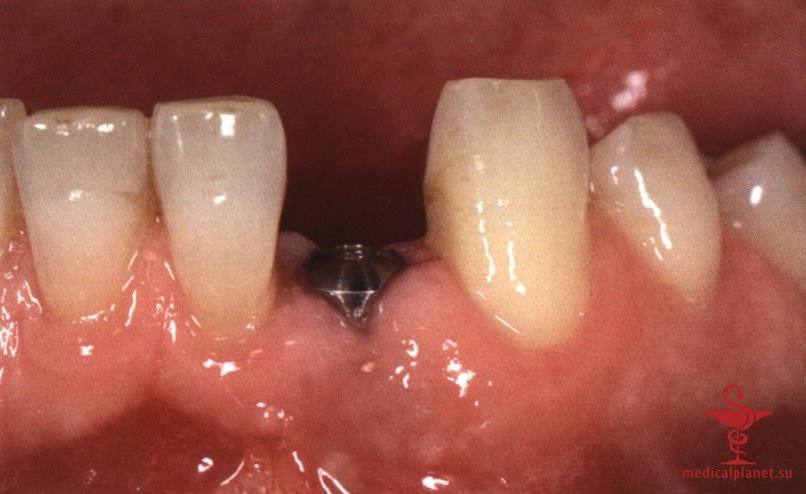

в) Отслаивание лоскута при одноэтапной имплантации. Одноэтапная немедленная имплантация кажется предпочтительной, поскольку герметичное ушивание раны сразу после удаления зуба представляется нецелесообразным. Вместо плотного сопоставления краев раны на имплантат немедленно фиксируют формирователь десны или временную реставрацию, что снижает риск деформации прилегающих мягких тканей.

Следует помнить, что любой, даже самый маленький лоскут требует наложения швов в области сосочков, а каждый разрез в этой зоне ведет к уменьшению их высоты, как обсуждалось в отдельной статье на сайте (просим Вас пользоваться формой поиска по сайту выше) (рис. 3). Иными словами, при немедленной имплантации в эстетически значимой зоне нужно избегать отслаивания лоскута.